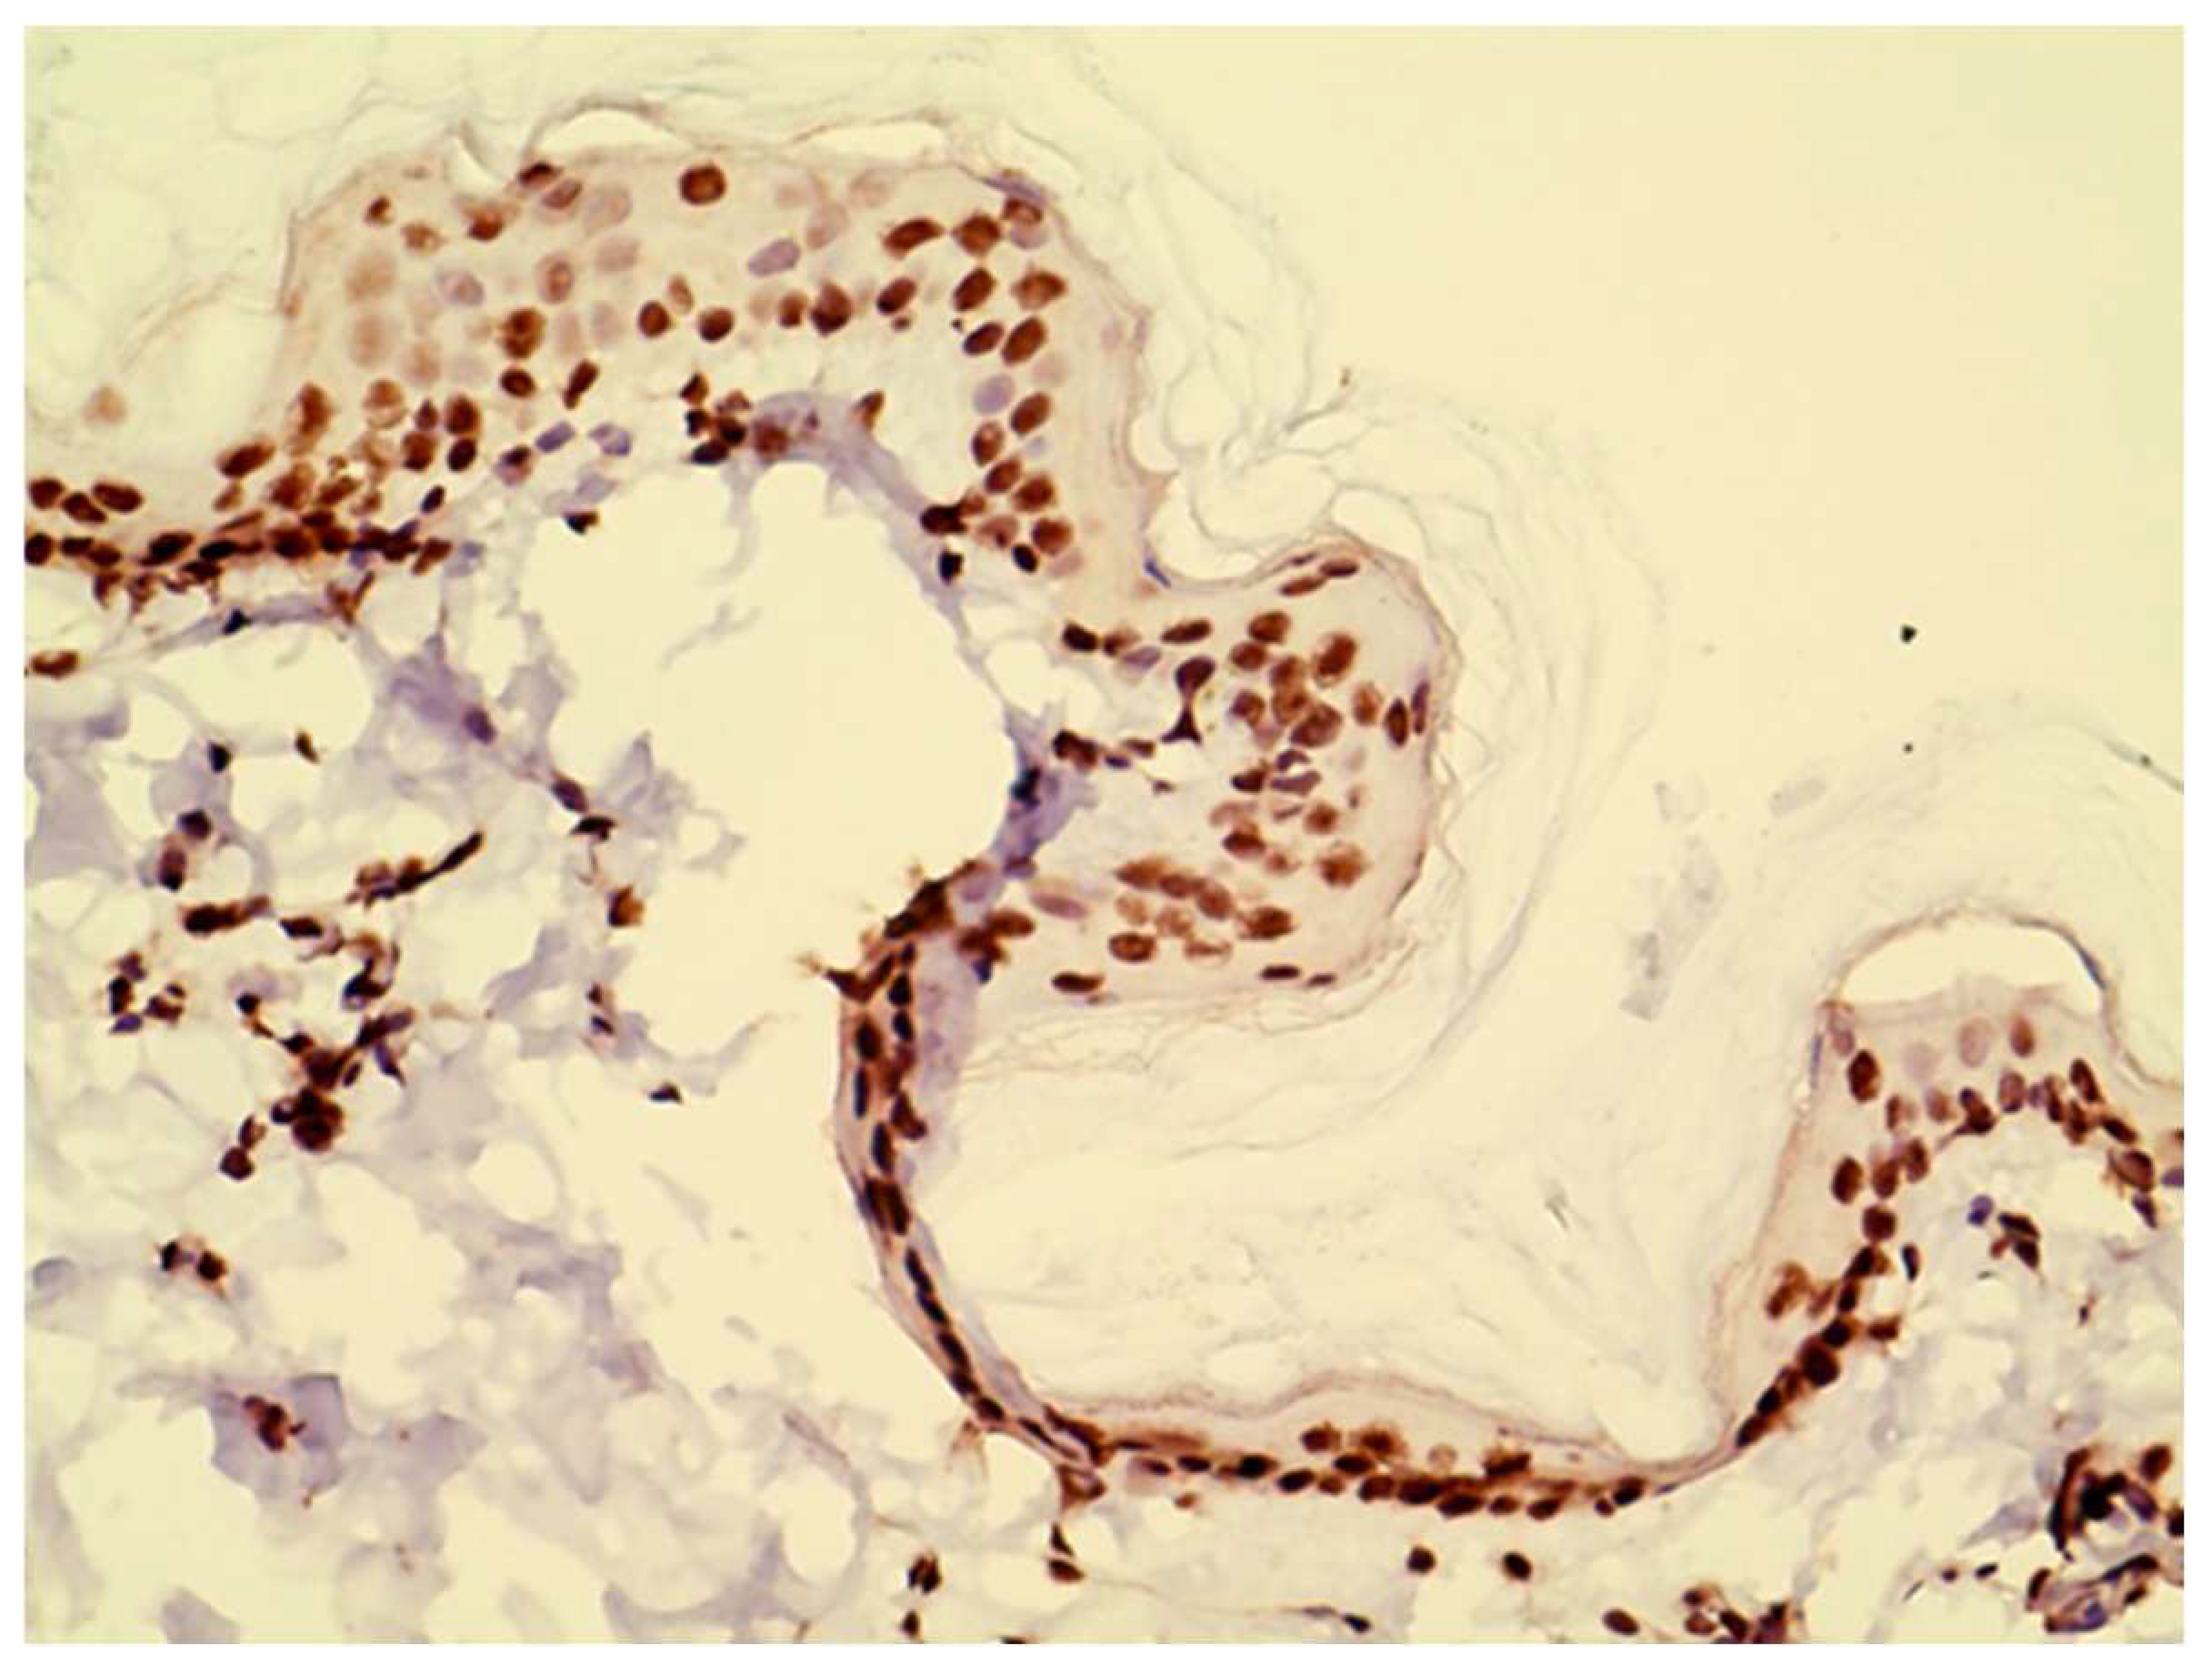

JAK1 and JAK3 staining was detected in both epidermis and dermis. JAK1 staining was cytoplasmic and primarily seen in basal keratinocytes and on dendritic cells (Figure 1). JAK3 was nuclear at all levels of the epidermis and on inflammatory cells in the dermis. (Figure 2 and Figure 3).

Figure 1. Example of JAK1 staining visible in the cytoplasm of basal keratinocytes and in dermal cells.